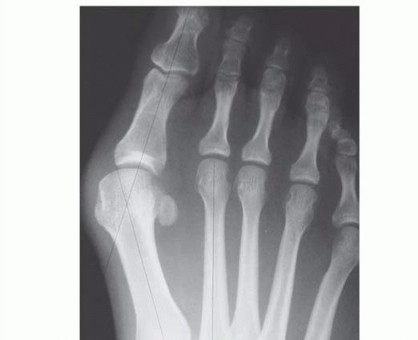

DEFINITION Correction of major bunion deformities through the proximal portion of the first metatarsal is wid…